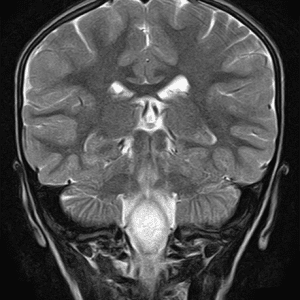

Nang màng nhện

Lượt xem: 154» 25-06-2020 -